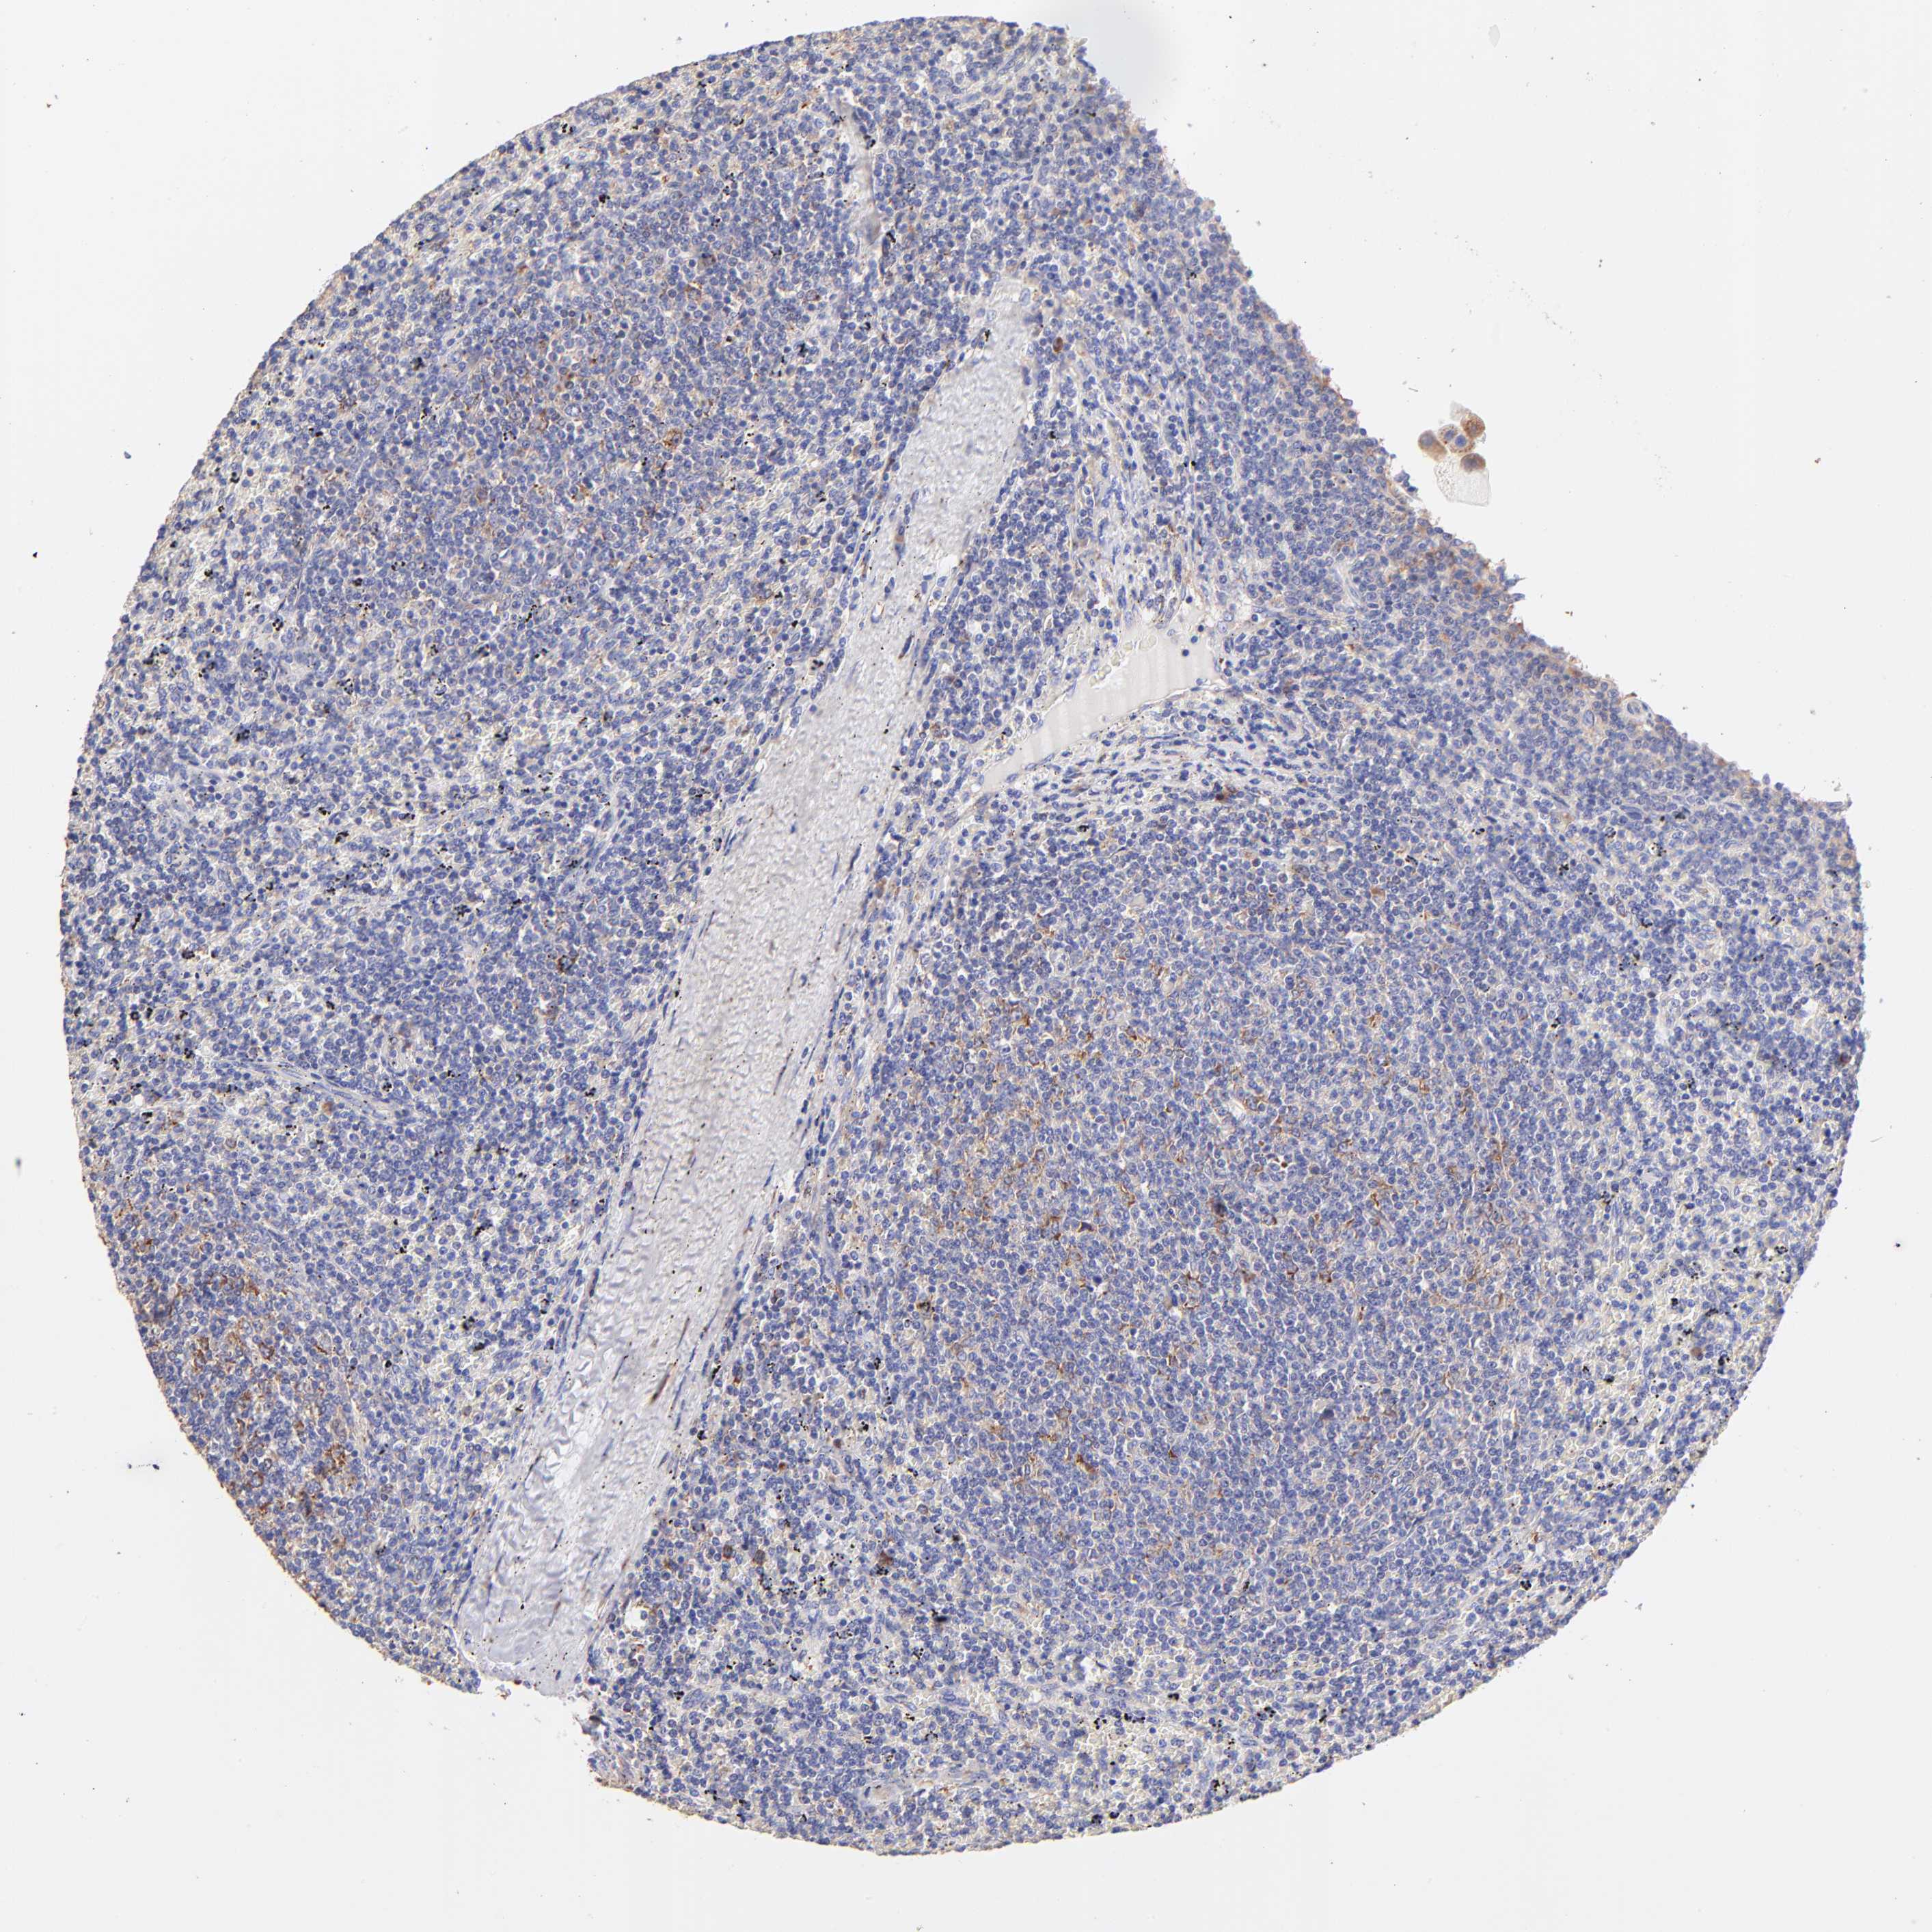

CANCER LYMPHOMA Show tissue menu

LYMPHOMA - Protein expressioni

A mouse-over function shows sample information and annotation data. Click on an image to view it in a full screen mode. Samples can be filtered based on level of antibody staining by selecting one or several of the following categories: high, medium, low and not detected. The assay and annotation is described here.

Each image is clickable and will lead to virtual microscopy that enables deeper exploration of all samples and also displays staining intensity scores, fraction scores and subcellular localization as well as patient and tissue information for each sample.

Antibody HPA002651

Staining

High

Medium

Low

Not detected

Intensity

Strong

Moderate

Weak

Negative

Quantity

>75%

75%-25%

<25%

None

Location

Nuclear

Cytoplasmic/membranous

Cytoplasmic/membranous,nuclear

Malignant lymphoma, non-Hodgkin's type, High grade

Malignant lymphoma, non-Hodgkin's type, Low grade

Hodgkin's disease, NOS